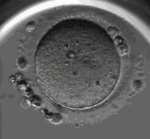

在促排期内会依据状况规定女性回院做检验,检验包含对卵巢的评定、检验卵子生长发育进而调整药物用量,当有子宫发育成熟了,就可以分配试管婴儿取卵了。在注入服药时,有一部分母亲会觉得肚子胀气可是不容易痛,大伙儿无需觉得太过焦虑不安。

在成功培养成试管胚胎以后,假如孕妈妈的身体情况比较好,医师便会分配移植,移植前尽量能够饮水憋尿,让子宫内膜视角光滑,那样更有益于试管胚胎嵌入。移植全过程不用麻醉剂,很有可能会出现少量不适感,但全过程是完全能够承受的。